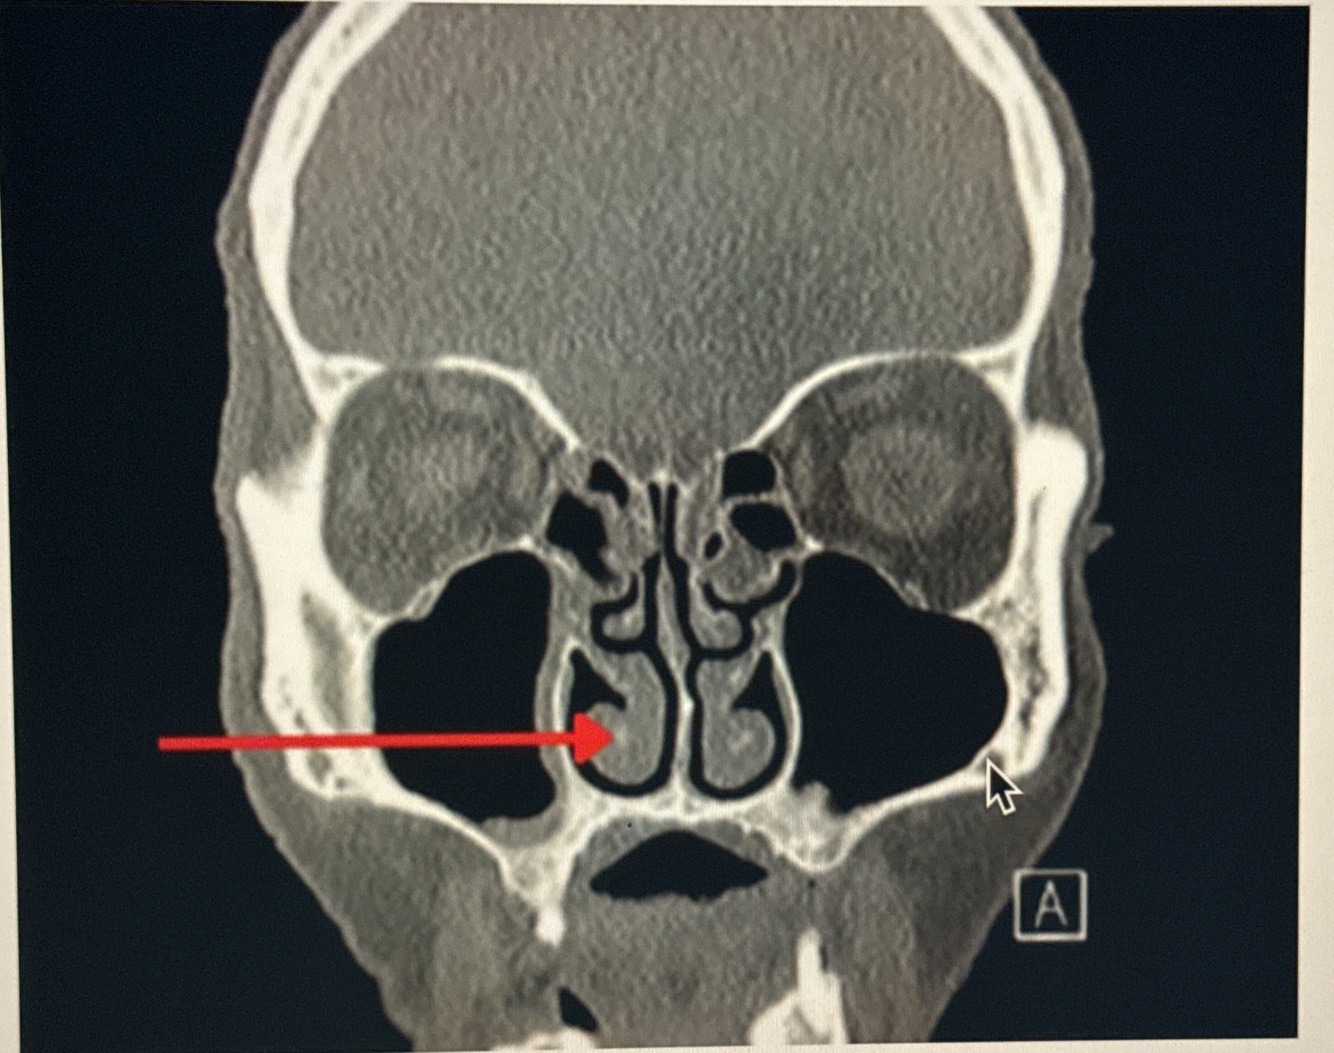

2

Q

A. Bony Nasal Septum

B. Middle Nasal Conchae

C. Inferior Nasal Conchae

D. Vomer

A